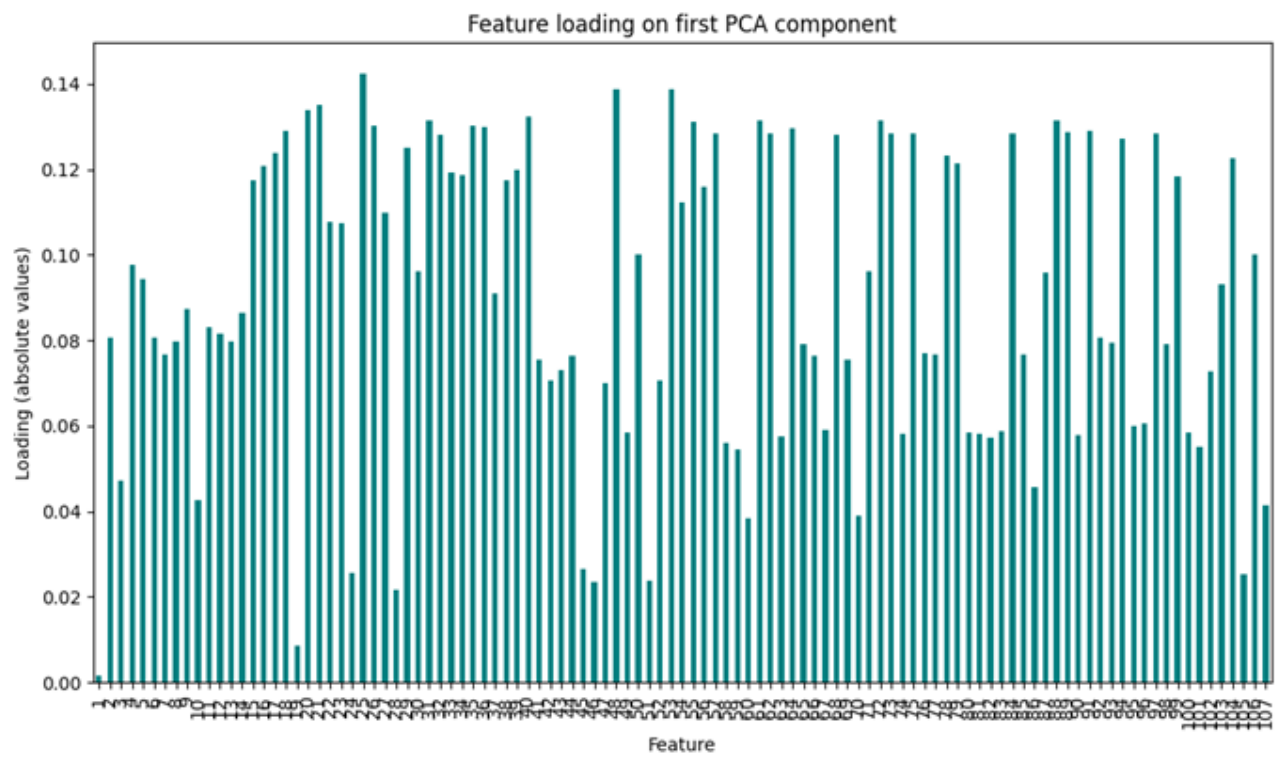

3.2. Radiomic Feature Interpretability and Clinical Relevance

4.1. Dimensionality Reduction